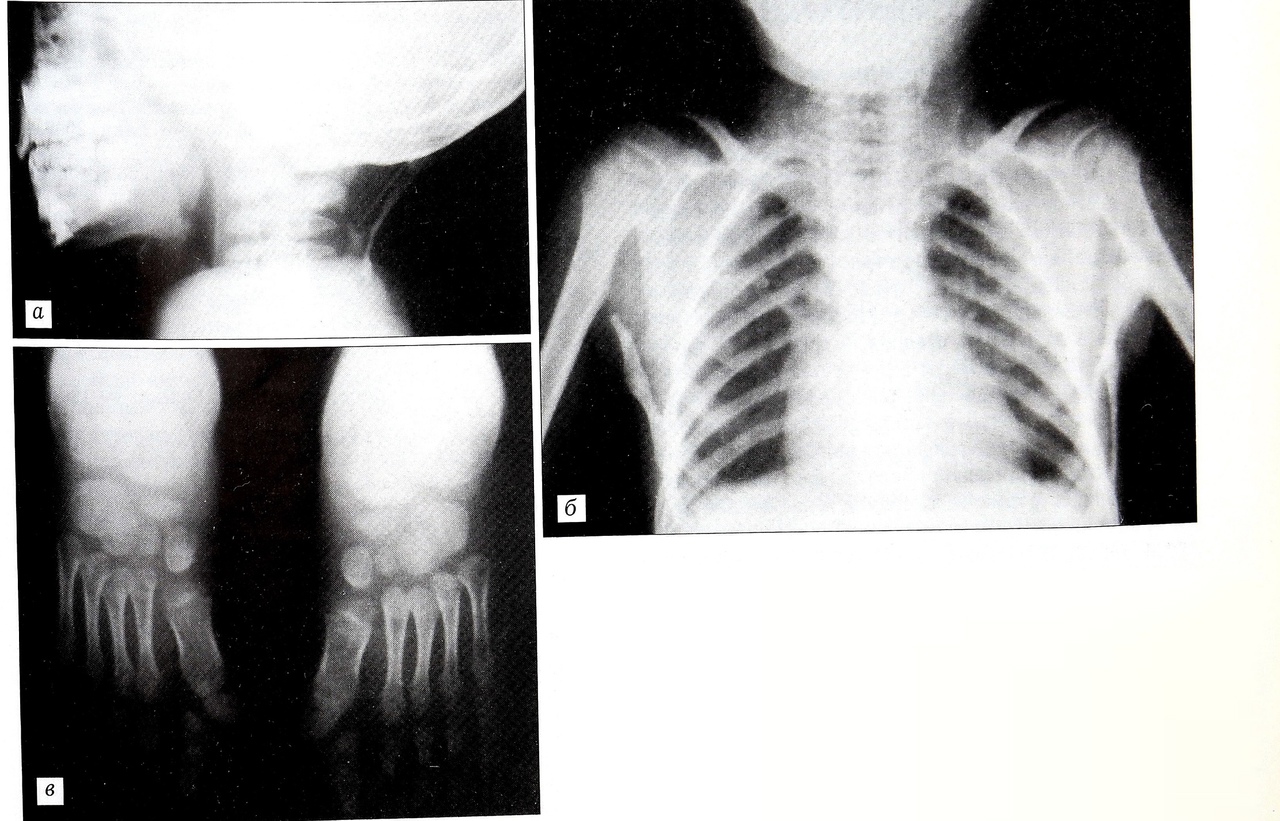

Рис. 1. Больной А. 4,5 лет.Диагноз: прогрессирующая оссифицирующая фибродисплазия.а — субфасциальный узел в области спины;б — характерный вид больного с ПОФ: полуоткрытый рот, короткая шея, наличие подкожных образований в подмышечных областях, отводящая контрактура в обоих плечевых суставах;в — симметричная микродактилия I пальцев обеих стоп с вальгусной деформацией в плюсне- фаланговых суставах.

Рис. 2. Рентгенограммы того же больного.a — боковая рентгенограмма черепа и шейного отдела позвоночника;б — прямая рентгенограмма грудной клетки; в — прямая рентгенограммы стоп.

При рентгенологическом исследовании скелета по левому краю С2-3 позвонков определяется соединяющая их гетеротопическая кость размером 3x0,6 см с четкими контурами. В боковой проекции обнаруживается соединение затылочной кости с остистыми отростками С5-6 позвонков эктопической костью в виде перемычки. Тела шейных позвонков короткие (рис. 2, а). В грудном отделе выявляются образования костной структуры продолговатой формы с четкими контурами, начинающиеся (слева двумя, справа одной ножкой) от костальной части VI—VIII ребер и идущие в направлении к задневнутренней поверхности верхней трети плечевых костей. Слева эктопическая кость широкой ножкой соединяется с плечевой костью, образуя внесуставной анкилоз в плечевом суставе. Справа костного соединения не отмечается. В надлопаточной области и по боковому краю шейных позвонков выявляются небольшие эктопические кости в мягких тканях. Нижние углы лопаток клювовидно деформированы и направлены к плечевой кости. Насчитывается 11 грудных позвонков с ребрами (рис. 2, б). Поясничный отдел без изменений. На прямой рентгенограмме на обеих стопах определяются микродактилия I пальца с аномалией метатарзальной и проксимальной фаланг, вальгусная деформация в первом плюснефаланговом суставе (рис. 2, в).